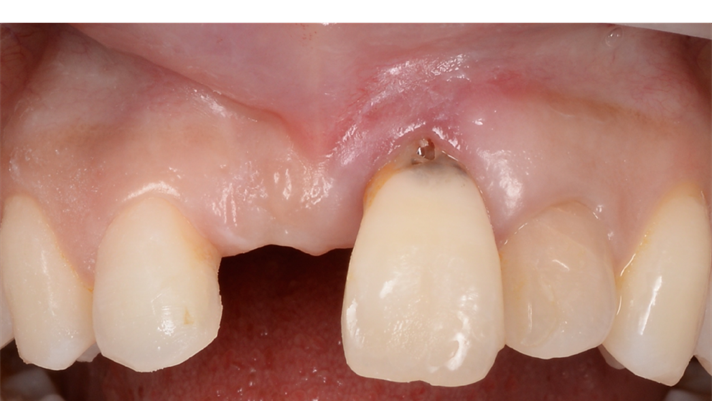

Clinical case: Patient-centered approach: treatment strategy for Root Membrane Technique & delayed implant placement

- Courtesy of Dr. Yoshiharu Hayashi, Japan -

Socket Shield Technique, anterior esthetics, maxillary anterior, esthetic, esthetics, delayed implant placement, socket preservation, AnyRidge, Root Membrane Kit, Root Membrane Technique, Partial Extraction Therapy, PET, esthetic zone, fuse abutment, Dr. Yoshiharu Hayashi,#11,#21,#22

AnyRidge implant system, fuse abutment Root membrane kit, PET Kit